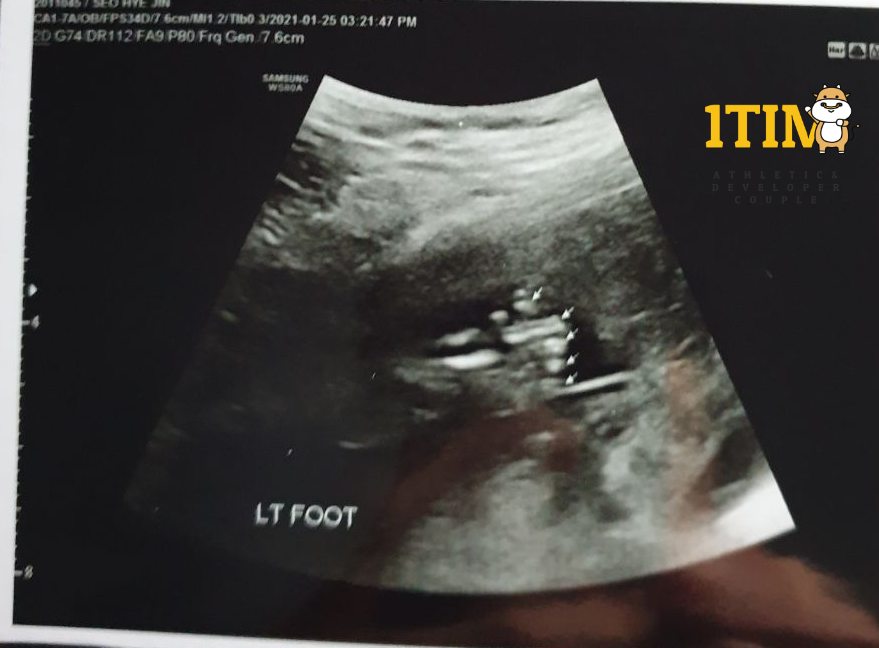

오늘은 한달만에 정기검진이 있는날. 정밀 초음파가 예정되어 있다.

양손가락/양발가락 갯수, 양쪽 귀, 입술, 코가 잘~~~ 붙어있는지 확인했다.

물론 정상 ~ 키키키 대견하구나.. 크롱군..